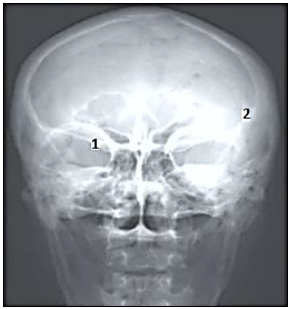

A afirmativa a seguir contextualiza a questão. Leia-a atentamente.

“Através do estudo anatômico, compreendemos a importância das imagens radiológicas do esqueleto axial e apendicular, sem distinção quanto à forma de aquisição, analógica ou digital.”

Com base na imagem radiológica, os números nela demonstrados representam, respectivamente, as seguintes estruturas anatômicas: